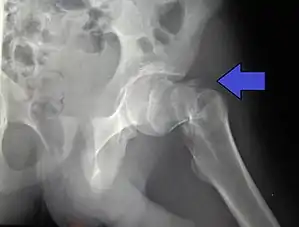

Intertrochanteric hip fracture in a 17-year-old male

Typically, radiographs are taken of the hip from the front (AP view), and side (lateral view). Frog leg views are to be avoided, as they may cause severe pain and further displace the fracture.[5] In situations where a hip fracture is suspected but not obvious on x-ray, an MRI is the next test of choice. If an MRI is not available or the patient can not be placed into the scanner a CT may be used as a substitute. MRI sensitivity for radiographically occult fracture is greater than CT. Bone scan is another useful alternative however substantial drawbacks include decreased sensitivity, early false negative results, and decreased conspicuity of findings due to age related metabolic changes in the elderly.

A case demonstrating a possible order of imaging in initially subtle findings:

X-rays of the affected hip usually make the diagnosis obvious; AP (anteroposterior) and lateral views should be obtained.